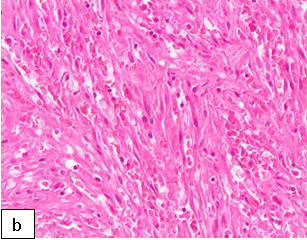

Diagnosis:Diagnosis is confirmed on histology which shows chronic granulomatous changes with cellular neoplasm composed of spindle cells with slit-like spaces containing red blood cells. Histoimmunochemistry test may be positive for HHV 8 which further confirms the diagnosis of KS.

Figure 161: (a) almost complete replacement of the nodal tissue by (b) a proliferation of spindle cells with slit-like vascular spaces. (Courtesy: Dr. Komala Pillay. Paediatric pathologist, Red Cross Children’s Hospital, Cape Town).